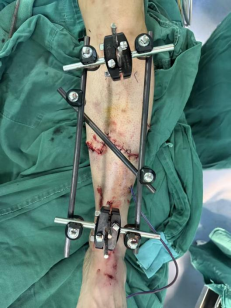

9.下肢严重开放性骨折,一期清创外固定支架固定+二期皮瓣修复创面